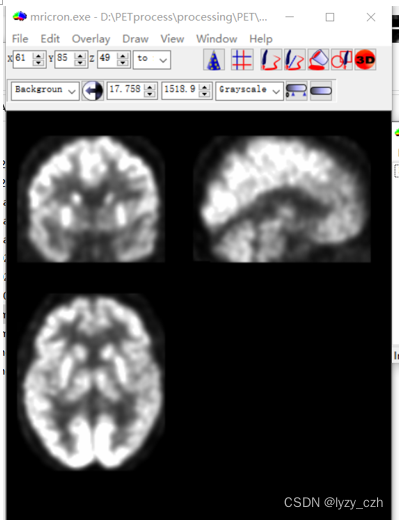

使用MRIcron打开hdr文件如下:MRIcron在我的之前的文章有介绍

点开wmeanxxxx.hdr如下:

打开output图像如下:

最后得到的图像如下: